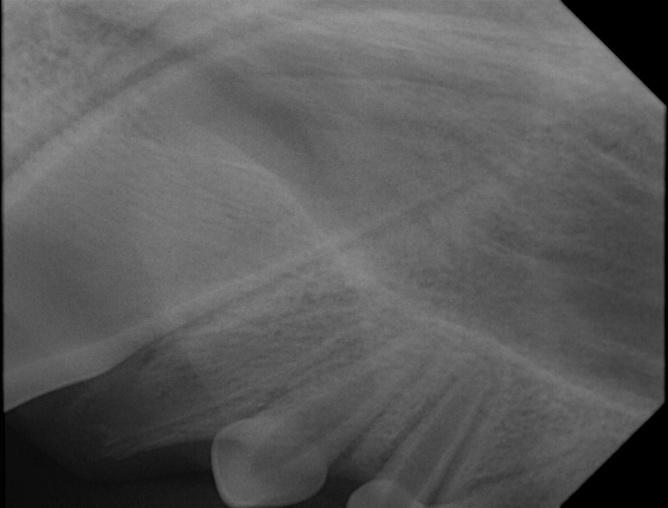

Siden tanna nå var knekt, førte dette til at tannen nå måtte fjernes kirurgisk. Som man kan se på tannrøntgenbildet før kirurgien, kan man se at det ikke er mye plass å jobbe på før man kan komme bort på den permanente tannen. Det ble derfor vanskelig kirurgi å utføre. Det måtte lages åpning i tannkjøttet med skalpell for å komme til rota. En slik operasjon gjennomføres ved at hunden legges i full narkose sammen med full overvåking av anestesipersonell som innebærer blodtrykksmålinger, oksygenmetningen i blodet, ekkokardiogram (puls og hjerterytme), væskebehandling intravenøs, pustefrekvens og temperaturmåling. I dette tilfelle måtte det også brukes lokalbedøvelse. Era var i trygge hender, rota kom ut, og såret ble sydd fint sammen.

Som du kan se på bilde nr. 2, er roten nå helt borte. Åpningen nederst ble sydd igjen, og Era fikk oppvåkning med full overvåking av dyrepleier og dyreassistent.